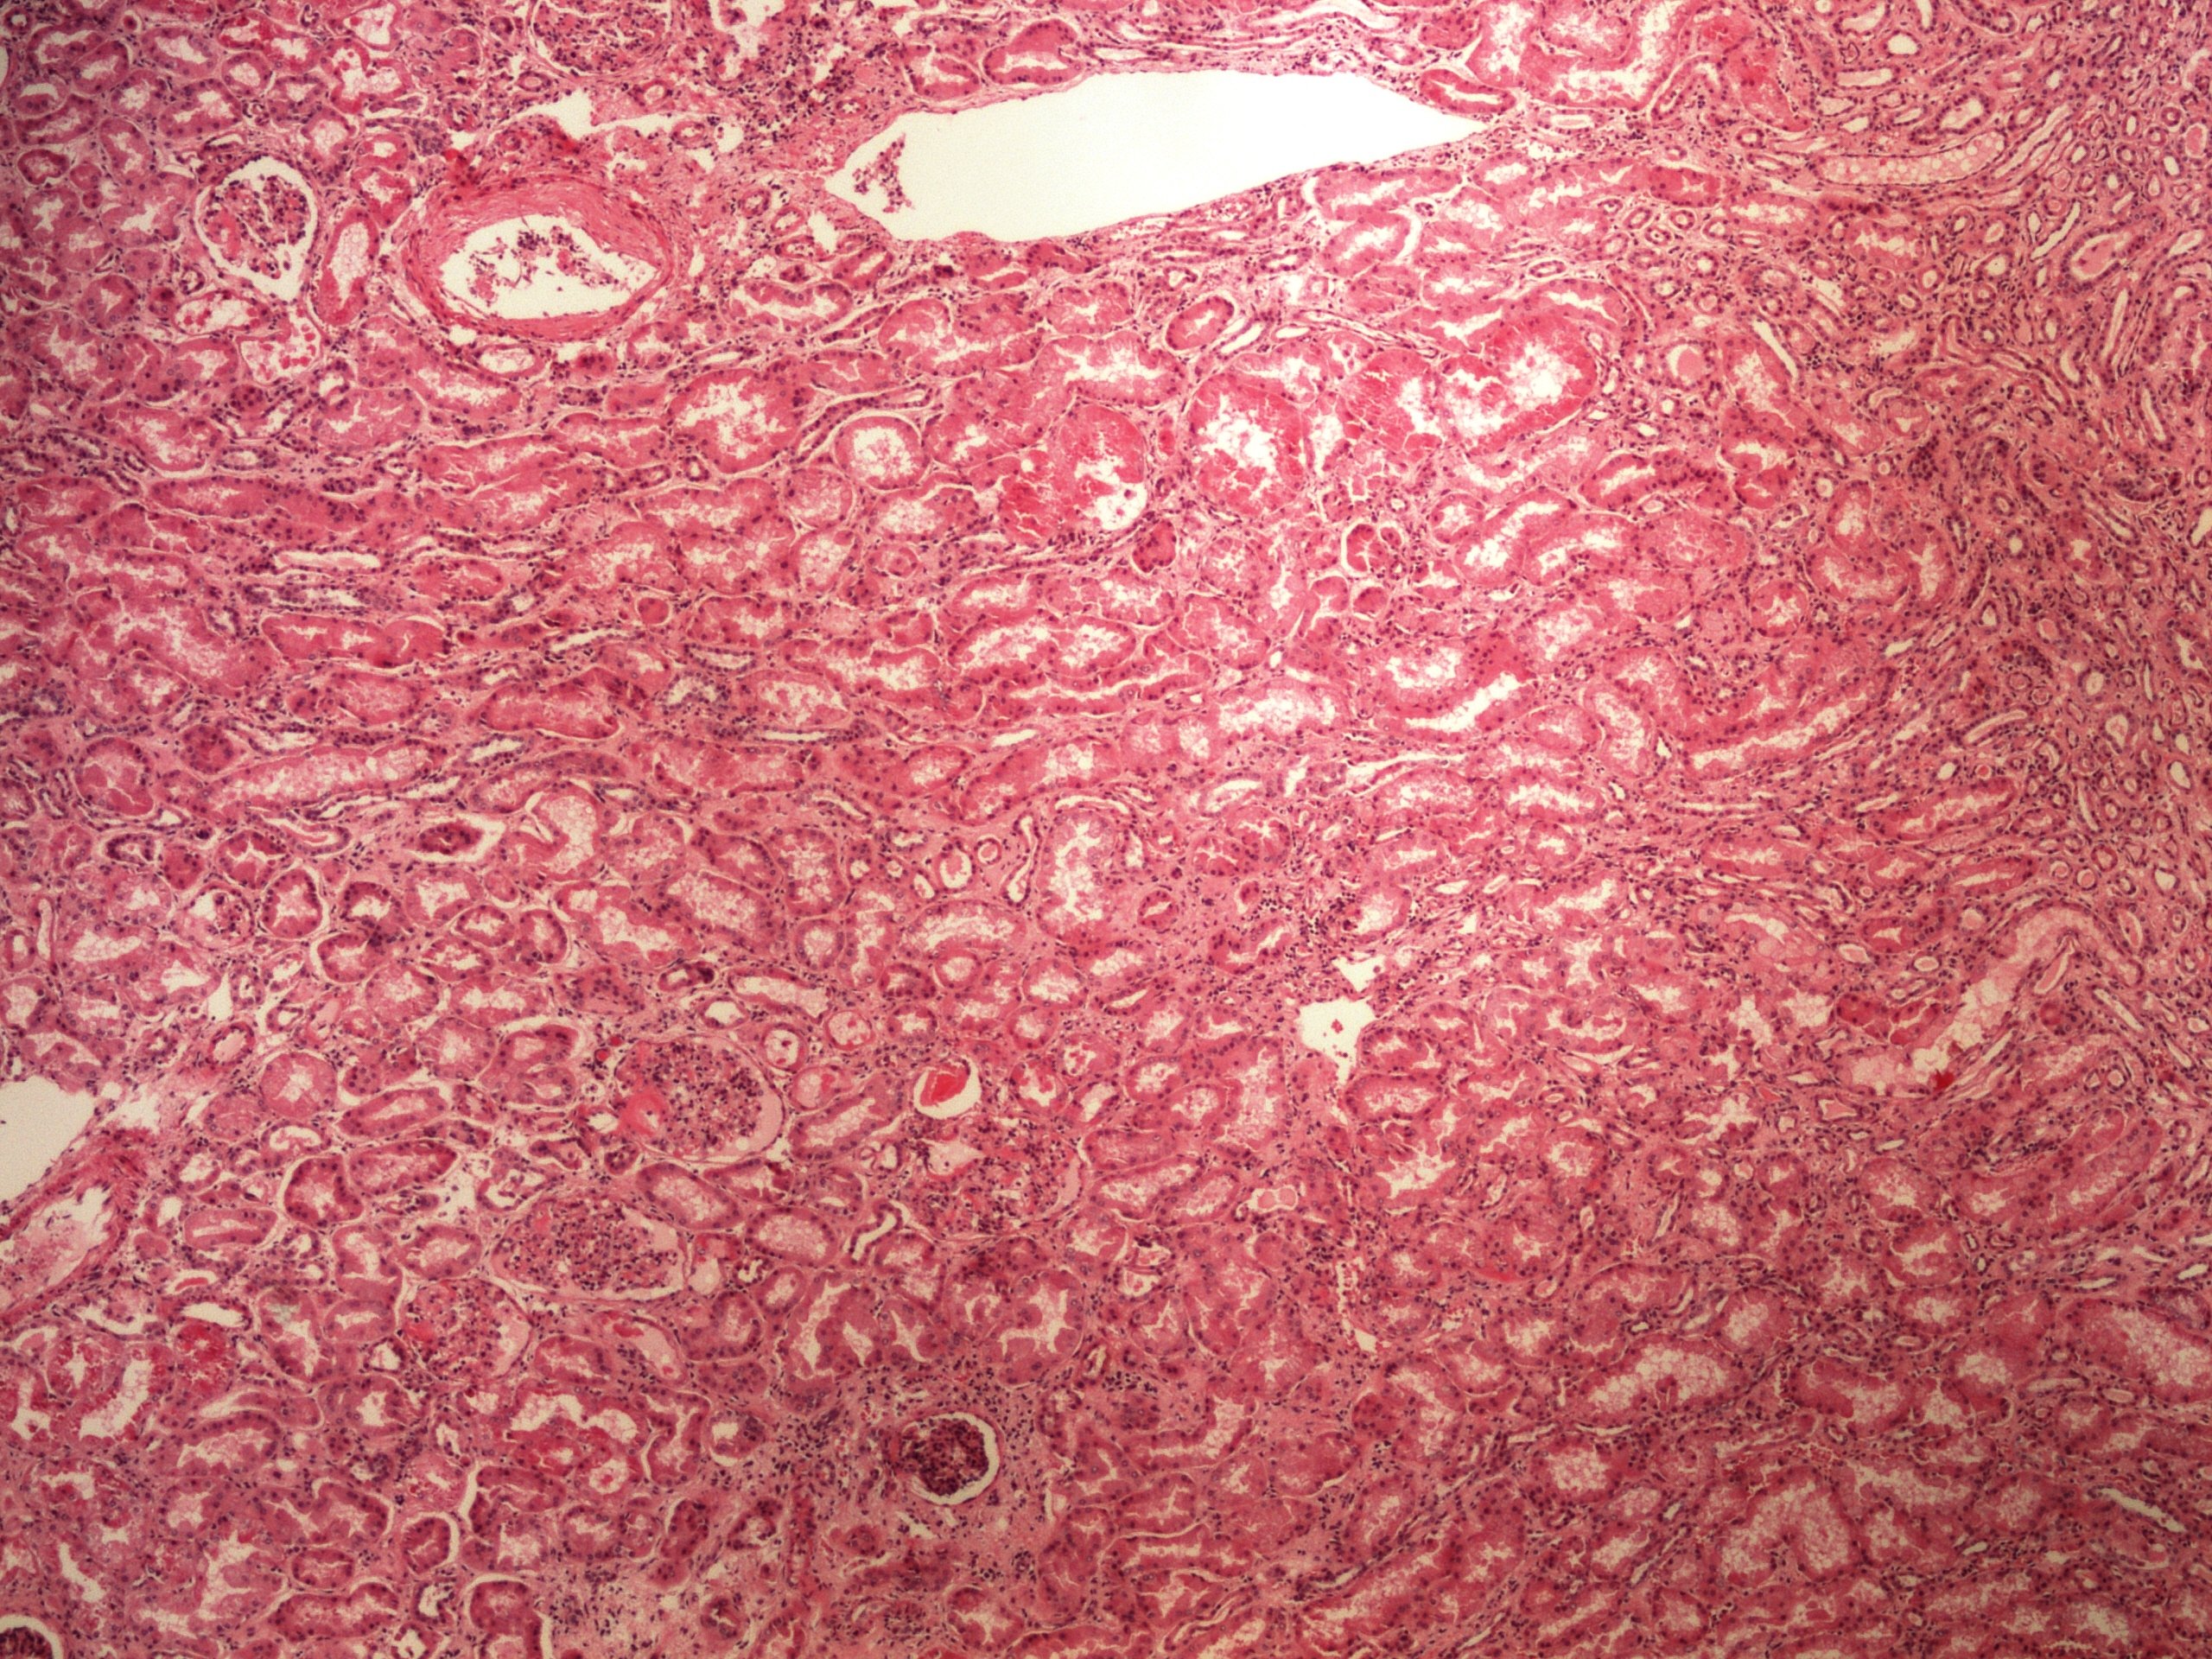

Preparát č.7 a č.8 - hyalinní zkapénkovatění ledviny

Struktury

- hyalinní kapénky

- tubulus